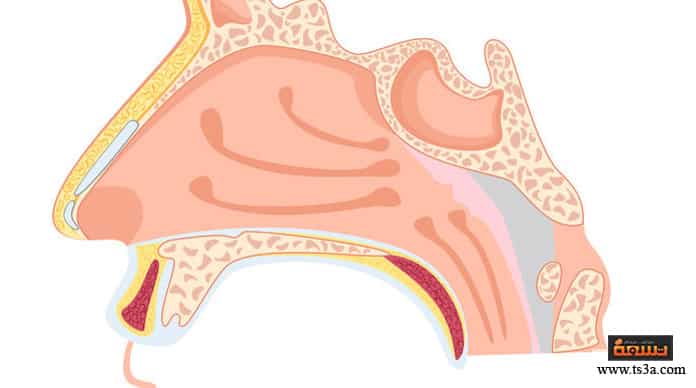

تمثل اللحمية عند الأطفال أحد المشكلات الشائعة الناتجة عن إصابة الطفل بالتهابات متكررة، حيث تؤدي هذه الالتهابات إلى تضخمها وهذا بدوره يترتب عليه حدوث عدة مشكلات مثل صعوبة التنفس، كما أنها تغير صوت الطفل ويظهر عليه الخنف، واللحمية في الأساس هي عبارة عن غدد لمفاوية موجودة لدى جميع الأطفال بشكل طبيعي، وتسمى لحمية عندما تتضخم مما يتطلب استئصالها في حالة كان هذا التضخم شديدا، أما إذا كانت غير متضخمة فلا يتم إزالتها وذلك لدورها الهام وفوائدها في مكافحة البكتيريا والميكروبات.

الغدد اللمفاوية موجودة عن الأطفال حديثي الولادة منذ ولادتهم، حيث أنها تلعب دورا هاما في الوقاية من الميكروبات والبكتريا، ولكنها قد يزداد حجمها وتتضخم عندما يصل الطفل إلى عمر السنة نتيجة للبكتريا والميكروبات، وقد تصبح أكثر تضخما عندما يبلغ الطفل عامه الثالث أو الرابع مما يتطلب إزالتها، وبالنسبة لحديثي الولادة فإن تضخم اللحمية يؤثر على قدرتهم على الرضاعة، وذلك نتيجة لانسداد فتحة التنفس في الأنف مما يدفع الطفل للتنفس بالفم ولذلك يكون من الصعب عليه تناول اللبن، كما أن اللحمية تسبب صوت الخنفرة من أنف الطفل نتيجة انسدادها وكذلك تسبب الشخير أثناء النوم، وقد تؤدي كذلك إلى إصابة الطفل بالتهابات متكررة في الأنف والجيوب الأنفية بالإضافة إلى التهابات الأذن الوسطى، ومن مخاطرها الشديدة انخفاض وظائف المخ والقدرات الدماغية نتيجة لقلة وصول الأكسجين للمخ، ومع مرور الوقت وتقدم الأعراض يتغير شكل وجه الطفل بسبب ضيق التنفس، ويسمى في هذه الحالة وجه أدينويد أو الوجه الأبله، حيث تبرز السنتان الأماميتان في الفك العلوي وترتفع الشفة العليا ويجف الفم والشفاه ويكون الفم مفتوحا باستمرار، بالإضافة إلى ضيق فتحتي الأنف بشكل ملحوظ نتيجة عدم استخدامهم بشكل طبيعي.